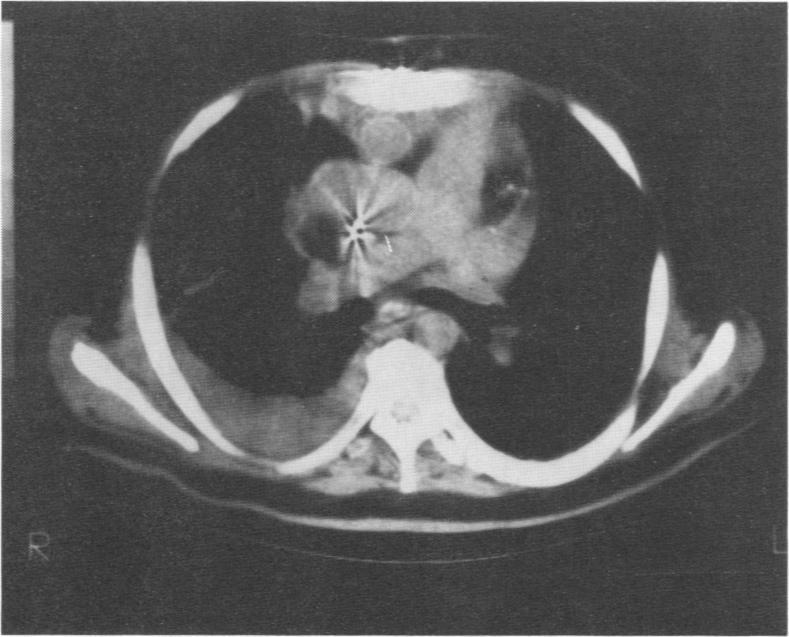

Seventy-three orthotopic and three heterotopic transplantations have been done in our institution, and in this report, we describe the procedure and outcome of those who underwent heterotopic transplantation. Three patients were in critical condition while awaiting donors for heart transplantation, and in each case, a suitable donor could not be found. Smaller donor hearts became available, and knowing that these patients would die without some kind of immediate action, we performed heterotopic heart transplantations. Patient Number 1 was a 53-year-old diabetic man who was in the last stages of heart disease when a small donor heart became available. Because of his rapidly deteriorating condition, we did a heterotopic transplantation. The patient is presently well and functioning normally. Patient Number 2 was a 26-year-old woman who received the heart of a 13-year-old donor after it became obvious that she could not wait for a suitable donor. We performed a heterotopic transplantation, after which the patient continues to function well. Patient Number 3 was a 53-year-old man who weighed 260 lbs. When a suitable donor could not be found, the heart of a 170-lb man became available and was used in a heterotopic transplantation. This patient also continues to be active and well. After considering the various advantages and disadvantages of heterotopic transplantation, we are convinced that there is a definite place for this procedure in some patients with end-stage cardiac failure, although we still believe that orthotopic transplantation should be offered to most recipients.